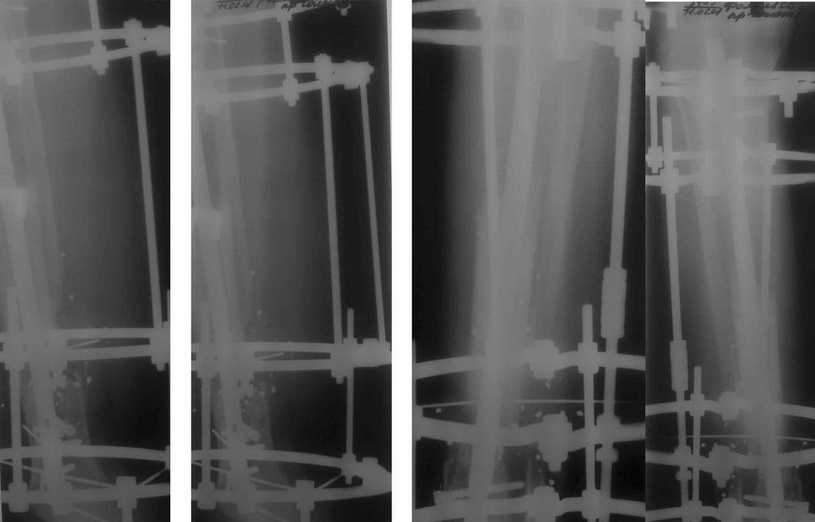

Больному была выполнена операция. после демонтажа аппарата Илизарова столкнулись с "прямо на глазах" сокращением регенерата. Гвоздь сквозь регенерат удалось провести без технических трудностей. Сложности были с репозицией отломков, что связано с выраженным остеопорозом, их короткими размерами. Пришлось применить полер-винт. Выполнили блокирование. По причине укорочения регенерата пришлось повторно смонтировать аппарат Илизарова и начать транспорт фрагмента на гвозде (14 мм). Больному разрешена ходьба с дозированной нагрузкой на больную ногу. Контрольные рентгенограммы прилагаются. Нынешняя ситуация породила ряд вопросов и замечаний: